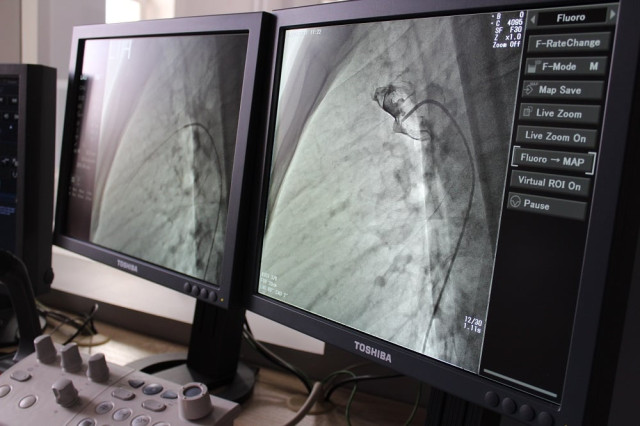

Вона була складною і проводилась під рентгенівським контролем із застосуванням ангіографа, під місцевим знечуленням (без наркозу). Через прокол у стегновій вені і артерії в незакриту протоку встановлено оклюдер (маленьку пружинку), яка перекрила потрапляння артеріальної крові у венозне русло.